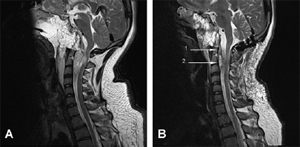

An intracranial resection of the tumour as far as the apex of the dens via an endoscopic endonasal approach (EEA) was performed (Fig. 2A). Following a stereotactic assisted bilateral endonasal exposure performed by an ear-nose-and-throat surgeon, a clivectomy was performed from the sella turcica to the foramen magnum. The tumour bulk was removed and the brainstem decompressed until pituitary dura was noted and the lateral magnus was clear. The anterior C1 arch and C2 odontoid process were then drilled and prevertebral and epidural tumour was removed. The lateral

gutters were also explored. Cranial nerves VI, IX, X, and XII were decompressed extradurally. The deficiency was repaired with an abdominal fat graft. Operative time was 18 hours. Postoperative MRI showed residual extradural tumour dorsal to the dens and the body of C2 extending to C3/4 and through the right C2/3 foramen, abutting the right vertebral artery (Fig. 2A). Furthermore, there was a smaller nodule of tumour occupying

the left side of the epidural space at the C1/2 level.

Subtotal microsurgical resection of the remaining tumour was carried out under endoscopic guidance 2 days later (Fig. 2B) with

Fig. 2. (A) Sagital T2-weighted MRI following the first operation – an intracranial resection of the tumour as far as the apex of the dens. Compression of the spinal cord from the remaining tumour mass is still apparent. There is a fat graft in place where the tumour has been removed. A catheter with balloon has been inflated to tamponade the fat graft against the surgical bed. (B) Sagittal T2-weighted MRI following the second operation – subtotal microsurgical resection of the remaining tumour under endoscopic guidance. (1) A small volume of residual tumour is seenposterior to the superior half of the odontoid peg. (2) Haemostatic material was placed anterior to the dura at C2/C3 due to excessive bleeding.